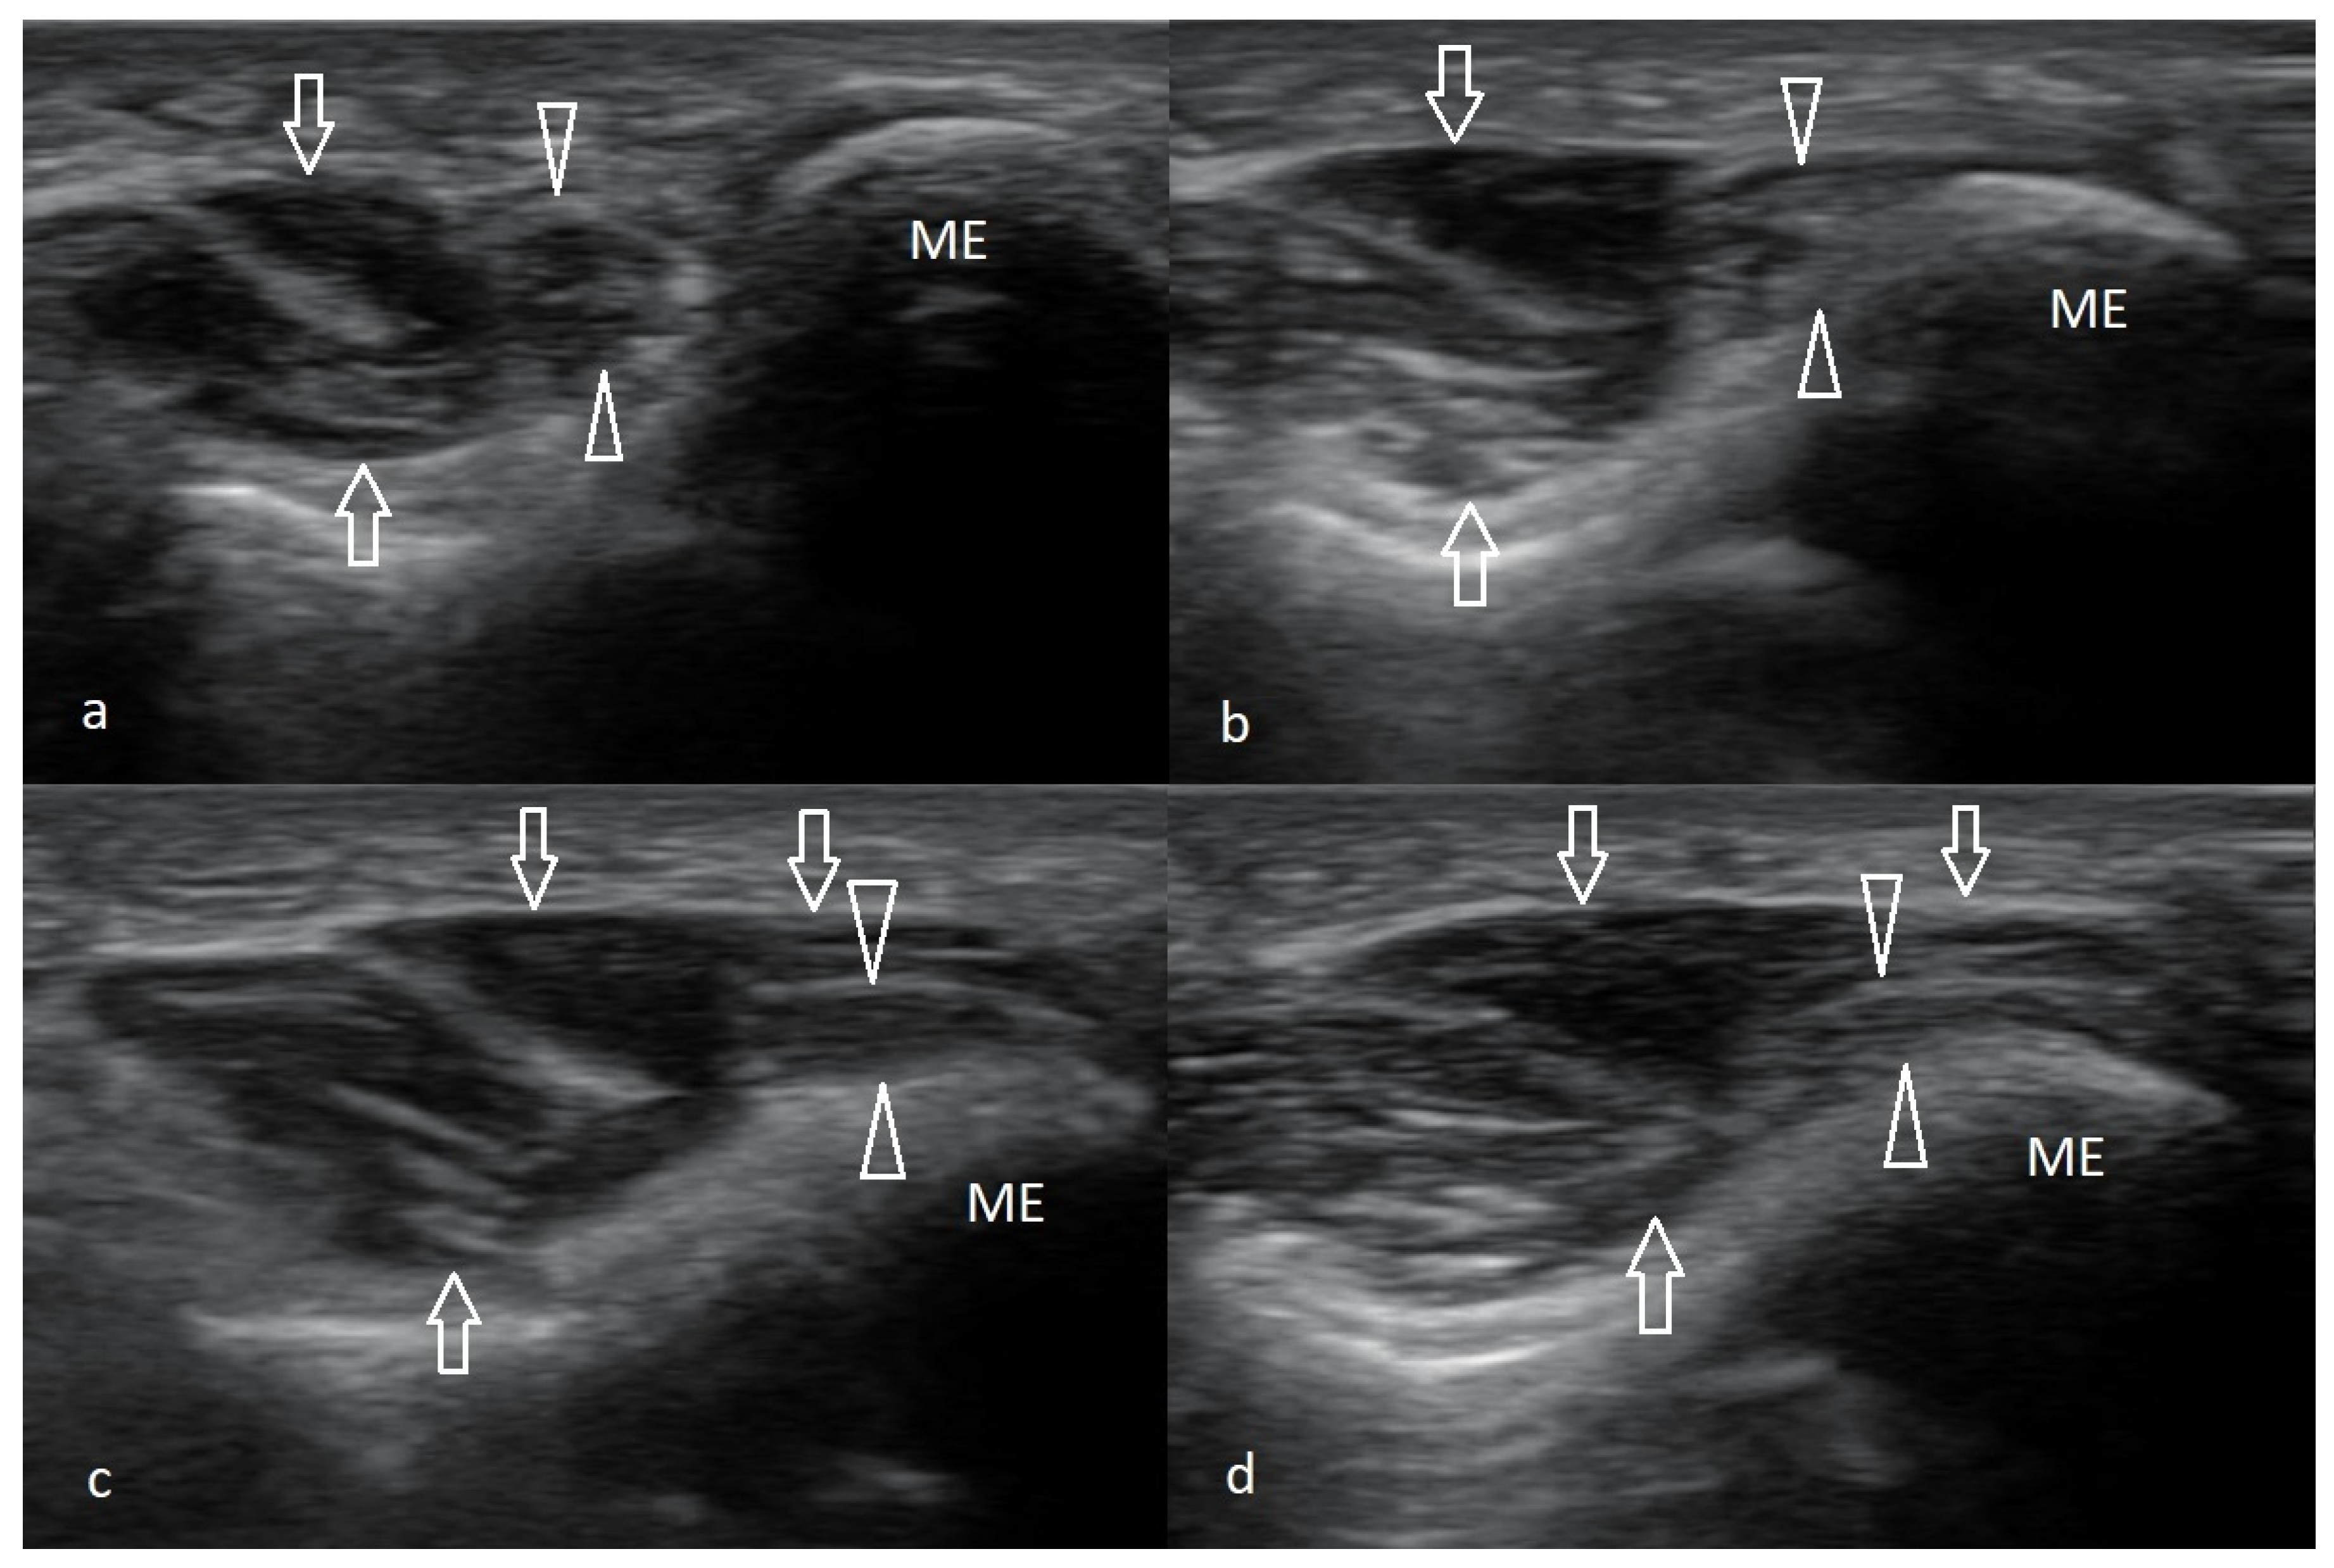

The Technique of Ultrasound Examination of the Medial Portion of the Elbow

4.2. Snapping Triceps with Ulnar Neuritis

4.3. Ulnar Nerve Compression Caused by Anconeus Epitrochlearis